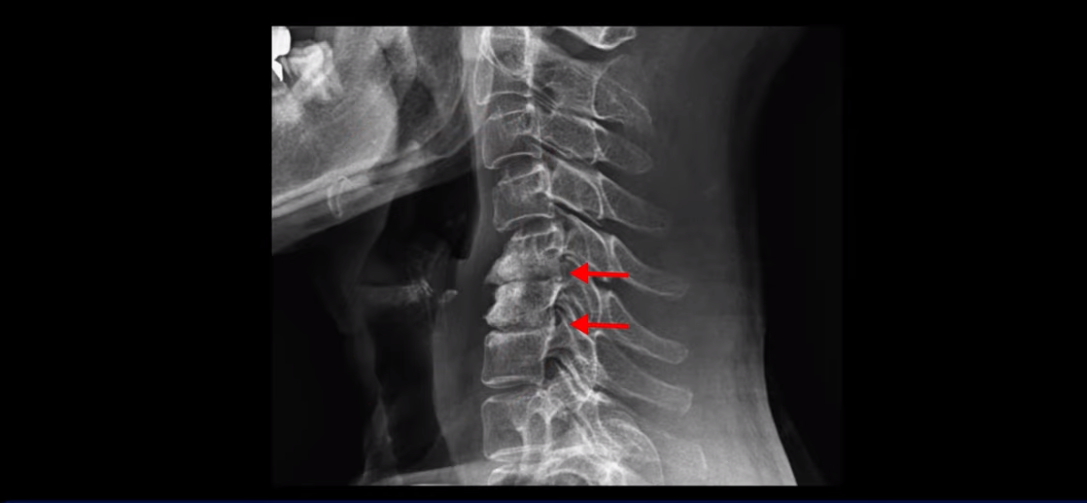

MRI를 보면 2마디 디스크의 퇴행이 아주 심해 보입니다.

그래서 오른쪽 신경 가지가 빠져 나가는 추간공 2개와

왼쪽 추간공 두 개가 모두 많이 좁아져 있습니다.

이렇게 신경 구멍들이 좁아져 있고 신경 주사가 효과가 없으니까 동네 정형외과에서는 무조건 대학병원으로 가라고 했는데요. 가서 수술 받으라는 얘기겠죠. 그런데 저희 모커리한방병원은 협착증은 수술 없이 치료가 잘 될 수 있는 질환이라고 계속 설명하고 있는데요. 왜 그럴까요? 저희가 협착증이 왜 수술 없이 치료 가능하다고 설명하는지에 대해 잘 이해하시려면 무증상 협착이라는 개념에 대해 잘 이해하셔야 합니다.